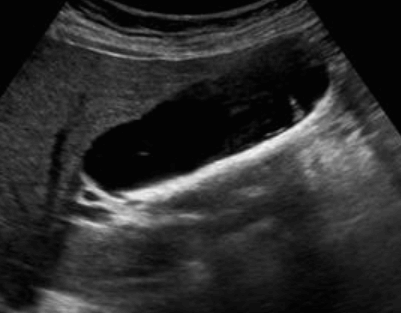

- 강한 고에코의 반사체 (strong echogenic sign)

- 후방음향음영 (posterior acoustic shadow)

- 환자 체위에 따라 움직임 (rolling stone sign)